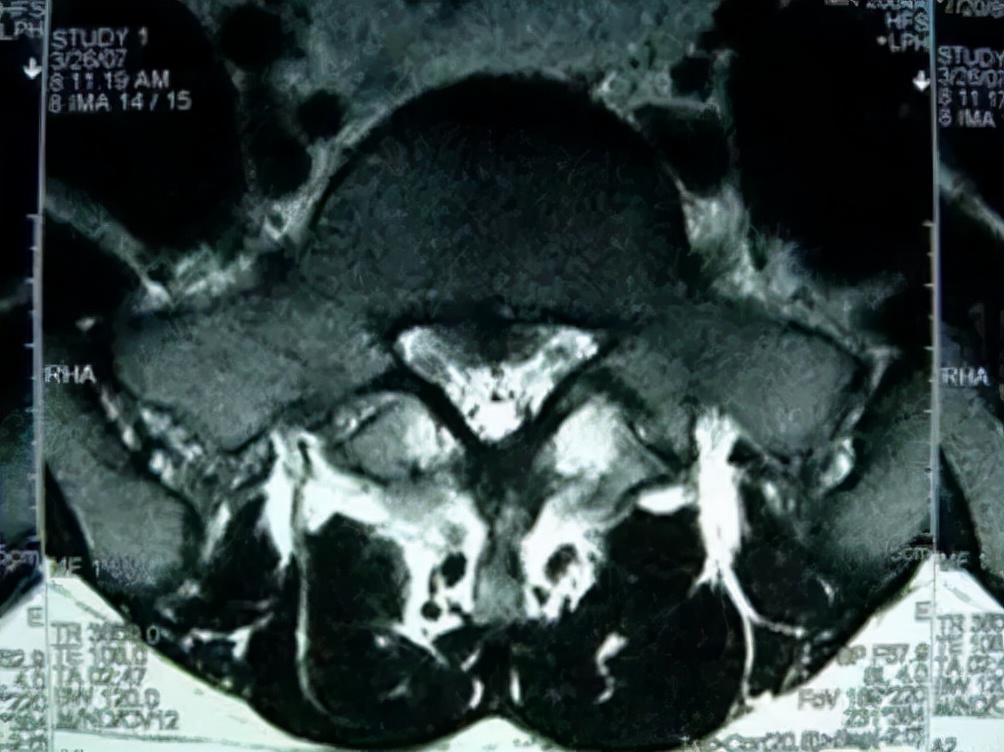

图:16岁男孩,腰痛(VAS 2分)伴右下肢放射痛(VAS 6分)26个月,L5-S1椎间盘突出,保守治疗无效,椎间孔镜后症状缓解。

Spine脊柱